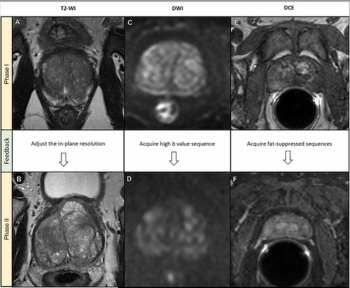

Utilizing a deep learning-based AI algorithm to differentiate between diagnostic and non-diagnostic quality of prostate MRI facilitated a 10 percent higher specificity rate for diagnosing extraprostatic extension on multiparametric MRI, according to research presented at the recent RSNA conference.